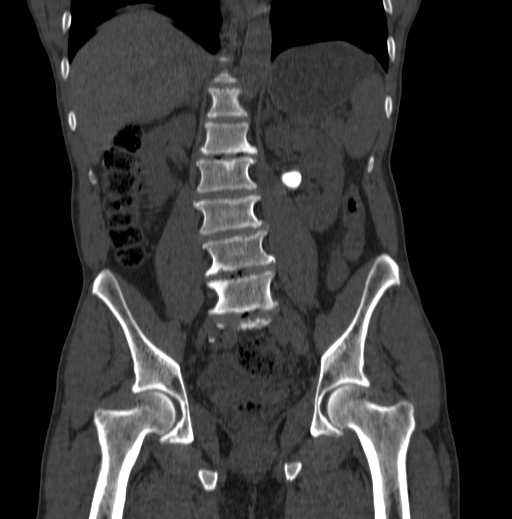

Case 3: Nephrostomy on Apixaban

Scenario: 70M with obstructing stone, febrile, pyonephrosis. On apixaban for DVT (CrCl 40).

Scenario: 70M with obstructing stone, febrile, pyonephrosis. On apixaban for DVT.

Plan: - Emergent nephrostomy needed

• Hold apixaban, but proceed with procedure

• Reversal options: Andexanet alfa (factor Xa inhibitor) or PCC if bleeding occurs

Evidence: SIR guidelines suggest holding DOACs for high‑risk procedures, but in emergencies, proceed with caution. Reversal agents can be considered if bleeding occurs.

Take‑home: In emergencies, prioritize patient stability. Hold DOACs if possible, but don’t delay critical interventions. Know your reversal options.